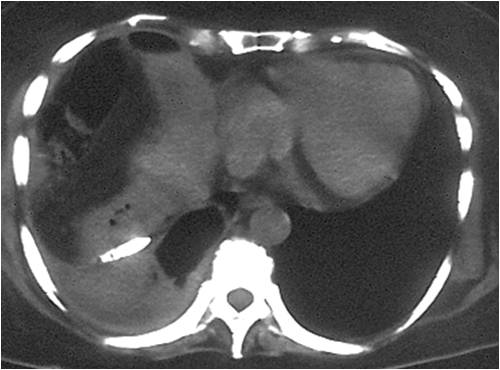

- Successful placement in sub-hepatic abscess post right hemicolectomy

- Abscess in gallbladder fossa post-colocystectomy

- Successful placement of catheter